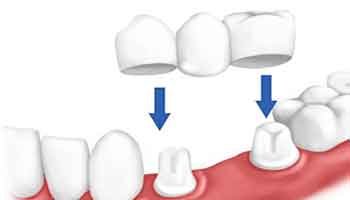

Por Dr. Diego Portnoi- White Smile Carillas Dentales Estética Dental.- Si necesitas un arreglo de un diente o tienes caries , la…

Por Dr. Diego Portnoi- White Smile Carillas Dentales Estética Dental.- Muchas veces una persona se encuentra con la necesidad de reponer un…